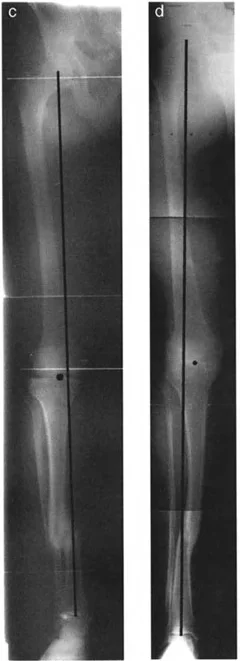

2. التصوير بالأشعة السينية (X-rays)

تعتبر الأشعة السينية هي الأداة التشخيصية الأساسية لتشوه الانزياح. يتم التقاط صور متعددة من زوايا مختلفة (عادةً الأمامية-الخلفية AP والجانبية LAT، وقد تشمل صوراً مائلة Oblique) للحصول على رؤية شاملة للتشوه.

- تحديد مستوى الانزياح: تظهر الأشعة السينية بوضوح المنطقة التي حدث فيها الانزياح.

- قياس حجم الانزياح (Magnitude): يتم قياس المسافة التي تحركها أطراف العظم بالمليمترات.

- تحديد اتجاه الانزياح (Direction): يتم وصف اتجاه الجزء البعيد من العظم بالنسبة للجزء القريب (مثلاً: أمامي، خلفي، إنسي، وحشي، أو مزيج منها).

- تحديد مستوى الانزياح (Level): يتم تحديد المنطقة التي تتداخل فيها أطراف العظم، والتي غالباً ما تكون مرتبطة بالتقصير.

- تقييم التلامس العظمي: تساعد الأشعة السينية في تحديد مدى فقدان التلامس بين أطراف العظم، وهو مؤشر مهم لعدم التئام الكسور.

- الأشعة المائلة (Oblique Radiographs): في بعض الحالات، قد لا يظهر الانزياح بوضوح في الصور الأمامية-الخلفية أو الجانبية، مما يستدعي صوراً مائلة للكشف عن التشوه الحقيقي، خاصة في حالات الانزياح في المستويات المائلة.

5. قياس محور الحمل الميكانيكي (Mechanical Axis Deviation - MAD)

يُعد قياس محور الحمل الميكانيكي أمراً حاسماً، خاصة في تشوهات عظم الفخذ والساق التي تؤثر على مفصل الركبة. يتم ذلك باستخدام صور الأشعة السينية الطويلة التي تشمل الورك والركبة والكاحل. يساعد هذا القياس في: